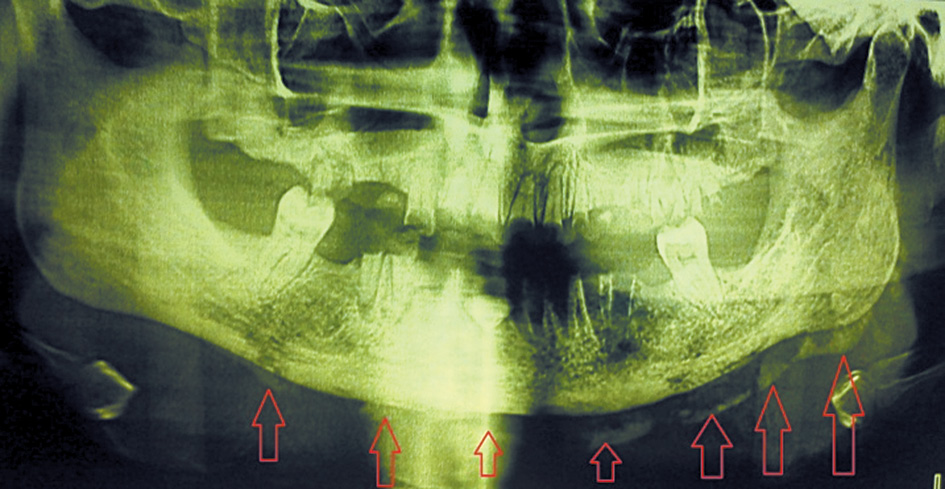

In addition, the sizes of sequesters varied from an isolated area of the alveolar process within 2–3 teeth to damage in half of the jaw and more. A characteristic was identified in 10 patients with a full-width mandibular lesion. A pronounced thickening and ossification of the surrounding periosteum were found in the form of stratification with the formation of a “bone sheath” surrounding the formed sequestrum, with a width of 5 mm to 1.2 cm (Fig. 2).

Fig. 2. The appearance of the line of ossification of the periosteum in the lesion area along the lower edge of the mandible, creating a “frame” of the newly formed bone / Рис. 2. Возникновение контура оссификации периоста в зоне поражения по нижнему краю нижней челюсти, создающее «каркас» из новообразованной кости

Postoperatively, patients almost did not complain of soreness and impaired well-being. Subsequently, after 7–14 days (on average 10 ± 1 days), marginal epithelialization of the defect was noted, and patients were discharged with improvement for outpatient treatment. No functional impairments (restriction of mouth opening, impaired swallowing, speech, and food intake) in 10 patients, including a lesion zone for the entire thickness of the lower jaw, were revealed since a dense “sheath” of the ossified periosteum that surrounds the affected part of the lower jaw was formed in this group of patients during the sequestration period, which caused the formation of a strong frame and the lack of mobility of the affected jaw fragments after surgery (Fig. 5).

Fig. 5. A newly formed bone along the lower edge of the mandible prevented the displacement of fragments after sequestrectomy / Рис. 5. Новообразованная кость по нижнему краю нижней челюсти предупредила смещение фрагментов после проведения секвестрэктомии

This prevented the dislocation asphyxia and lower jaw deformation, as well as the emergence of functional disorders in the maxillofacial region. The shape of the jaw was preserved, and therefore the replacement of the postoperative defect with implant materials was not indicated. This avoided the additional stages of the surgery and accelerated the defect epithelialization. In addition, the occurrence of pathological fractures was not registered in the postoperative period. Complete epithelialization of the defect walls occurred on days 12–39 from the surgery (on average of 21 ± 1 days) and depended on the size of the removed sequestrum (Fig. 6)